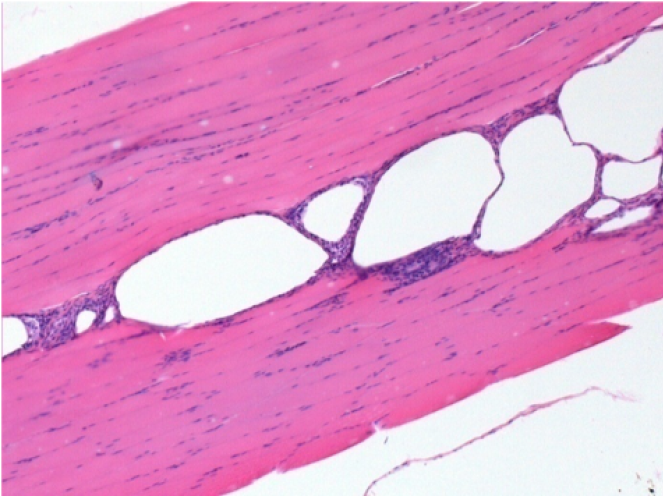

7 meses después de la inyección de Endopeel

7 meses (D210) después de la inyección IM de Endopeel 0,1 ml en el músculo pretibial derecho.

Restitutio ad integrum (restauración a la condición original) completa después de 7 meses

L : Control-100xD210

R:100xD210

L :Control 50xD210

R50X-D210